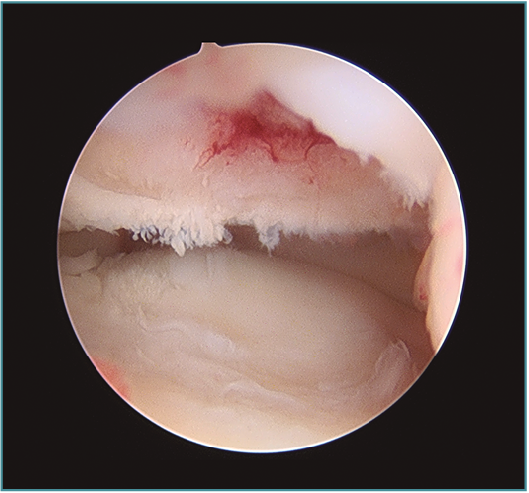

Pueden ampliarse los portales 1 cm a modo de mini-open para facilitar la extracción del fragmento libre articular o la fijación del mismo si fuera necesaria (Figura 7). Una vez extraído el cuerpo libre, se puede refrescar la zona origen del defecto con un sinoviotomo o incluso realizar unas perforaciones con un punzón o una aguja de Kirschner de 1,8-2 mm, con una separación entre ellas de 2-3 mm aproximadamente, para favorecer la creación de un tejido fibrocartilaginoso que proteja la zona (Figuras 8 y 9)(10). Por esta misma vía se pueden realizar técnicas complementarias como la introducción de matrices celulares o biogeles (véase más adelante).

Figura 9. Sangrado del hueso osteocondral tras perforaciones.